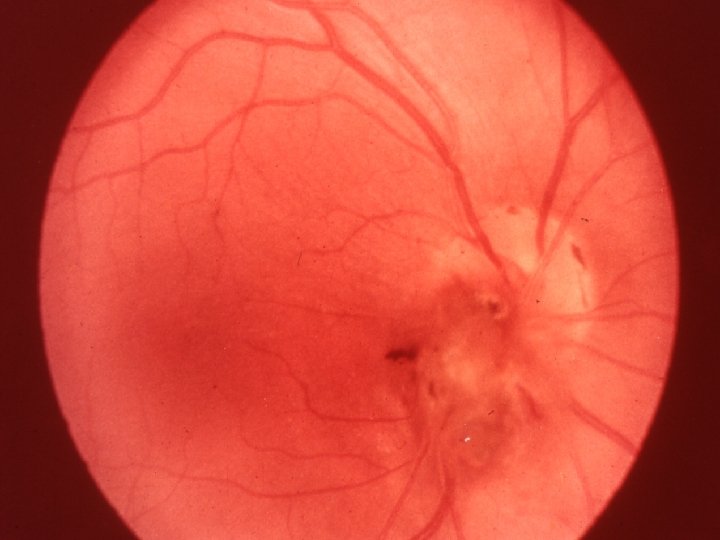

Traumatologie et Brûlures oculaires 2 - Contusions du globe Le syndrôme traumatique du S. postérieur Hémorragies rétiniennes Intra ou pré-rétiniennes: BAV , graves si touchent la région maculaire Intravitréenne: Pluie de suie, BAV brutale

Traumatologie et Brûlures oculaires 2 - Contusions du globe Le syndrôme traumatique du S. postérieur Ruptures choroïdiennes Stries jaunâtres bordées d’une hémorragie BAV ++ si touche la région maculaire Décollement de rétine Désinsertion à l’ora ou déchirure, peut apparaître plusieurs jours après le trauma BAV progressive, ttt chirurgical